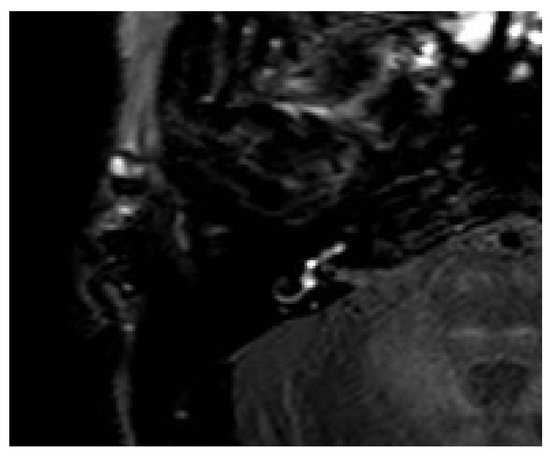

3.7. Case 7

Figure 7. An 84-year-old male presented with an acute hearing loss on the right side with rotatory vertigo. The contrast enhancement was seen in the right vestibulum and basal turn of the cochlea on the 4 h delayed 3D-FLAIR sequences.